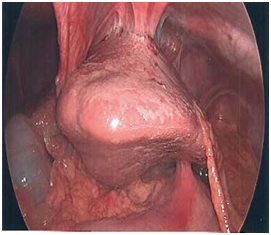

On physical exam, he was a febrile with normal vital signs and had a tender epigastrium without peritonitis. Given his cardiac comorbidities and chest pain, a coronary event was first ruled out with troponins and EKG. Other laboratory studies were significant for a WBC of 19.2. On imaging work up, his CXR showed no pneumoperitoneum and no acute cardiopulmonary processes. Given his history of upper abdominal pain and a h/o difficult laparoscopic cholecystectomy, a right upper quadrant ultrasound was obtained which showed a hypo echoic collection superior to the liver with a hyperechoic focus in it (Figure 1). A CT scan was obtained which showed a subphrenic fluid collection with a 2cm stone in it, a subhepatic fluid collection and moderate pericardial effusion. There was also a concern for a pericardial-peritoneal fistula (Figure 2).

Figure 2 A CT scan was obtained which showed a subphrenic fluid collection with a 2 cm stone in it, a subhepatic fluid collection and moderate pericardial effusion. There was also a concern for a pericardial-peritoneal fistula.